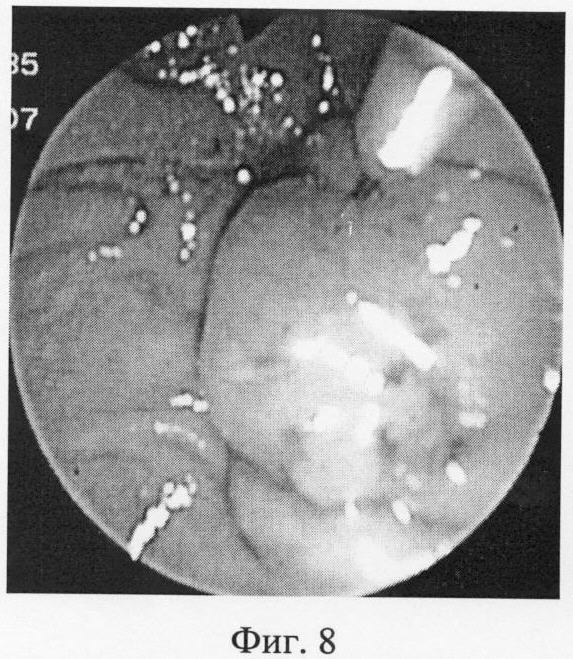

Фиг.8 – папиллотом установлен выше устья БСДК, электрод выведен из оплетки.